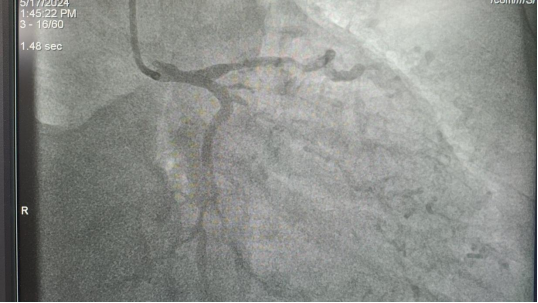

患者抵达我院后,通过绿色通道迅速完善了增强CT等相关检查。心内科主任张鹏及外二科主任韩东江紧急会诊,并根据心电图复查结果紧急行冠脉造影检查显示:患者左主干及三支血管均存在弥漫性病变,急性冠脉综合征的诊断得以明确(左主干+三支病变 前降支、回旋支、右冠脉重度狭窄),同时合并有嗜铬细胞瘤、腹主动脉溃疡、腹主动脉粥样硬化斑块、Ⅱ型糖尿病等。

通过医联体的无缝对接,高效沟通互动,经紧急救治,患者目前已恢复三级血流,转危为安,转入ICU优化药物治疗。